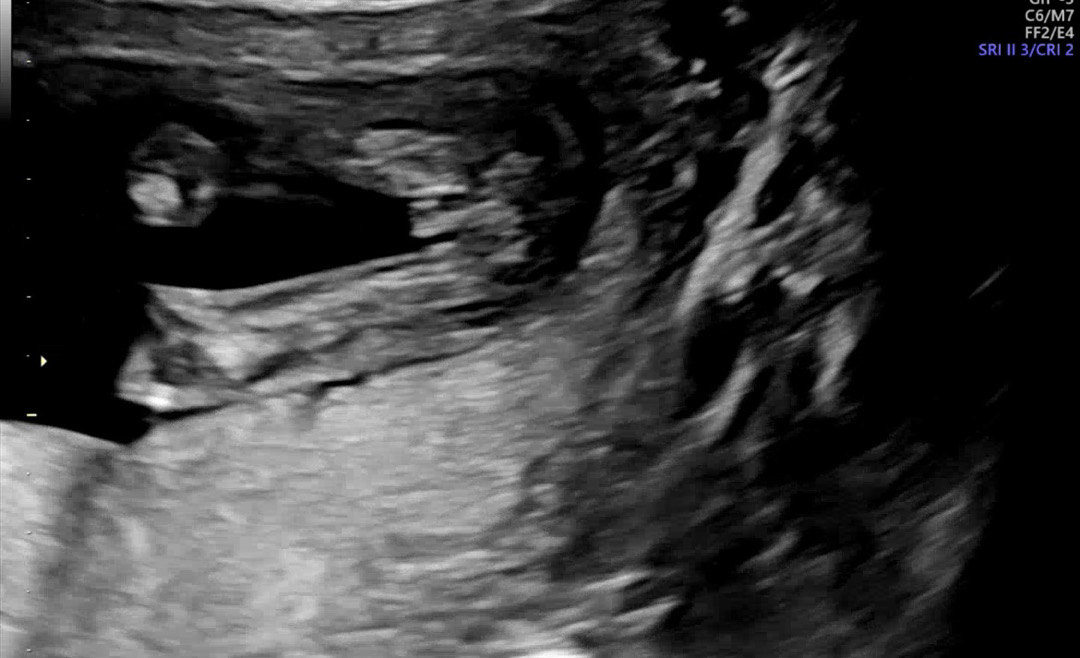

16주 성별 딸 맞을까요?

16주 의사쌤이 딸이라고 하는데 반전 없겠죠…??